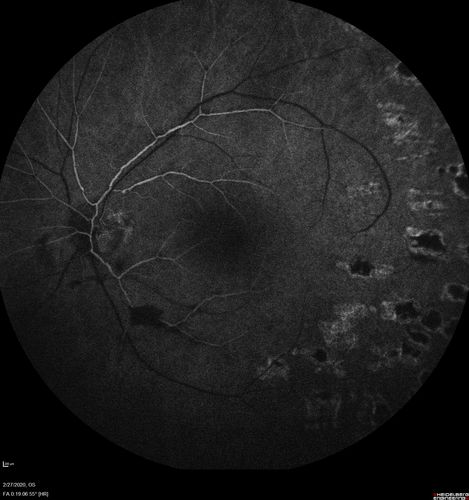

Eales Disease and fresh vitreous hemorrhage - 20 year old man

20 year old mane with fresh vitreous hemorrhage in the right eye.  At age 15 he had a PPV and laser in the left eye and laser in the right eye.  The vision is OD 20/80 PH 20/25, OS 20/25.  The left eye has a mild cataract.  He had prior testing for coagulopathies which was negative.  Testing done for syphillis and TB was negative.  Additional laser was done to prevent further bleeding in the right eye.